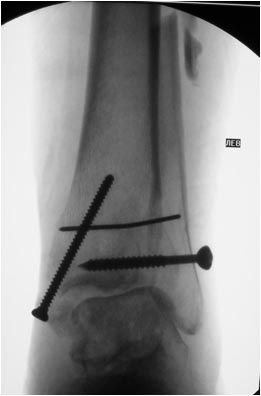

Мне кажется, что вопрос, поставленный Вами: "Возможно ли одномоментно устранить подвывих или только на аппарате Иллизарова?", отражает не совсем ясное понимание ситуации. Что значит устранить подвывих? А пластику ложных суставов внутренней лодыжки и заднего края большеберцовой кости не нужно делать? И ось голеностопного сустава нужно исправлять. То есть делать остеотомию наружной лодыжки (если она срослась, по снимку не очень понял). Артродез голеностопного сустава в такой ситуации очень сложен. Если же добиться сращения всех переломов в правильном положении, артродез вполне можно отсрочить на несколько лет, что для молодого пациента достаточно важно. Но в конечном счете все определяется Вашим умением и ясным представлением того, чего Вы хотите добиться своей операцией. Во вложении - в чем-то похожий случай. Оперировал эту пациентку 23 лет 11 лет назад через 8 месяцев после похожего на представленный Вами остеосинтез. На первой операции перелом малоберцовой кости в нижней трети был просто не замечен. За счет восстановления оси быстро развившийся артроз протекал благоприятно. В результате артродез был выполнен только в прошлом году, через 10 лет после второй операции. И боли беспокоили пациентку только в течение года перед артродезом.